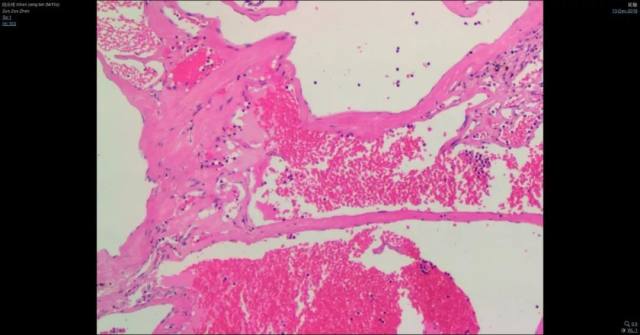

6、病理

送检脑组织中可见畸形的血管成分,伴出血及血栓形成、机化,局灶可见钙化,伴多量含铁血黄色沉积,符合脑血管畸形,请结合临床。

免疫组化结果:CD31(血管+)、CD34(血管+),GFAP(+),CD68(局灶+),Ki-67(约 2%+)